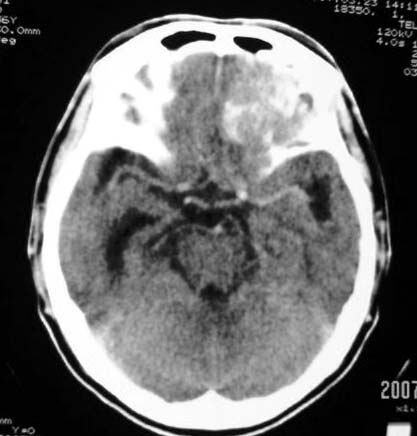

标题: CT7268:左额顶部病变增强片. [打印本页]

标题: CT7268:左额顶部病变增强片.

比较典型的少枝胶质细胞瘤ct表现,局部额骨垂直板有侵蚀变薄。

左额叶病灶内条片状高密度是钙化吗?是的话考虑少支胶质瘤可能大。不然有脑血畸形伴出血可能。

左侧额顶叶有条带状钙化的不规则形占位,增强呈不均匀轻度强化,局部颅骨受侵蚀变薄,典型的少支胶质细胞瘤。

比较典型的少枝胶质细胞瘤ct表现,局部额骨垂直板有侵蚀变薄